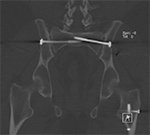

Complex cross-sectional geometry implants will result in streak artifact along the axes of greatest cross-sectional thickness (Buckwalter, 2011). In the presence of multiple implants the artifact will be most severe along the axis containing both implants. For example, with bilateral hip arthroplasties, the artifact will be most pronounced along the right-left axis as the beam travels through both implants (Figure 3). By orienting the hardware with shortest dimension of the implant perpendicular to the table, the amount of associated streak artifact will be reduced.

Artifact Summation. (A) Scout image demonstrates bilateral total hip arthroplasties. (B) Axial CT image at the level of acetabular cup and femoral head shows severe transverse streaking related to total summed attenuation of metal components. Optimal Windowing. (A) Axial CT image of the pelvis viewed in soft tissue windows demonstrates extensive streak artifact due to total hip arthroplasty prohibiting evaluation of adjacent bone and soft tissue structure. (B) Same axial CT image set to bone windows results in improved visibility of adjacent bone and soft tissue anatomy.